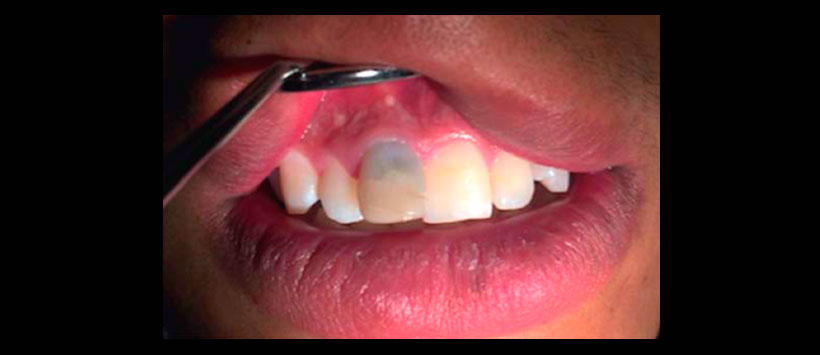

Paciente masculino de 19 años de edad, acude al Post- grado de Endodoncia de La Universidad de la Salle Bajío, León, México. Sistémicamente refiere alergia a la penicilina. Fue remitido para retratamiento endodóncico del incisivo central superior derecho, por presencia de sintomatología. El paciente refiere dolor a la masticación y tacto desde hace un año. Clínicamente se observó restauración en borde incisal del OD 11 y cambio de coloración del órgano dental en porción cervical, no se tamiento previo de endodoncia y en porción apical de la raíz aparentaba una desviación del conducto (Figura 1). Se diagnosticó como diente previamente tratado con periodontitis apical sintomática, por lo que se decidió realizar un retratamiento.